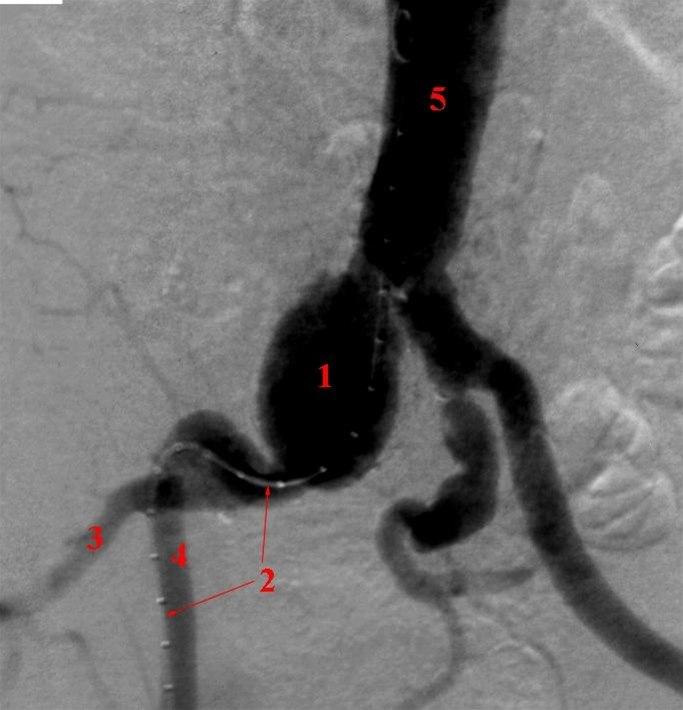

Aneurisme i høyre arteria iliaca communis.

- Aneurismet (utposning)

- Kateter

- A. iliaca interna

- A. iliaca externa

- Aorta